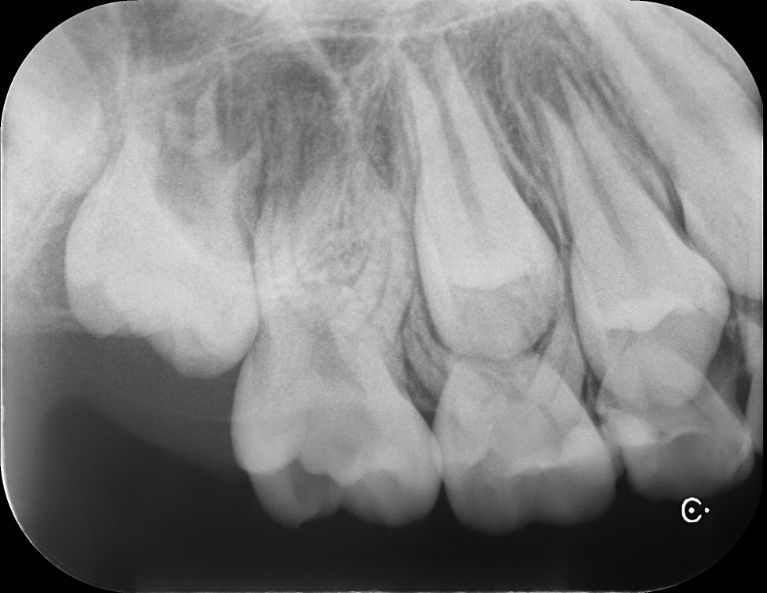

術前

| 治療説明 | 歯髄に到達する大変大きな虫歯がありました。まだ若い患者であり、通常通り根管治療を行うと、歯質が薄くなり歯の寿命に大きく影響すると考えました。う蝕と感染の疑いがある歯髄を除去し,正常歯髄をMTAセメントを用いて保存した上で、ダイレクトボンディングにて歯の形を回復しました。 |

| 治療回数・期間 | 1回 |

| 副作用とリスク | 歯髄が感染し根管治療が必要となる可能性があります。レジンの着色、破折が起こり、研磨や再修復が必要となる可能性があります。 |

| 料金(税込) | MTAセメント:55,000円 ダイレクトボンディング:55,000円 |